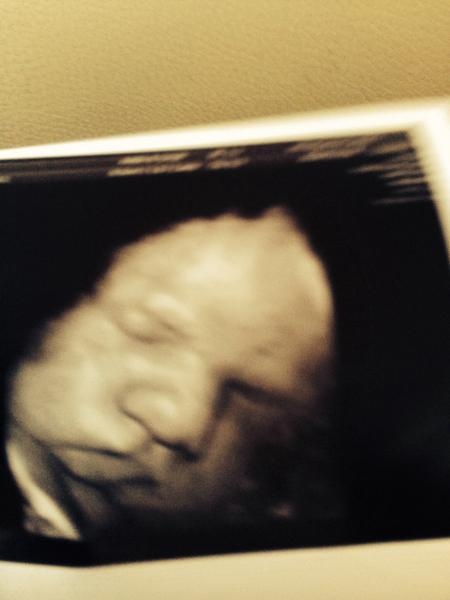

Denna graviditeten har jag också ett extra ultraljud pga grav-diabetes . Han ligger också lite över sin kurva men denna gången han jag än så länge bara gått upp 1 kg.

Får se vad de säger på söndag på ultraljudet .

Idag ska jag in på mitt sista ultraljud. Spännande men är nervös samtidigt.